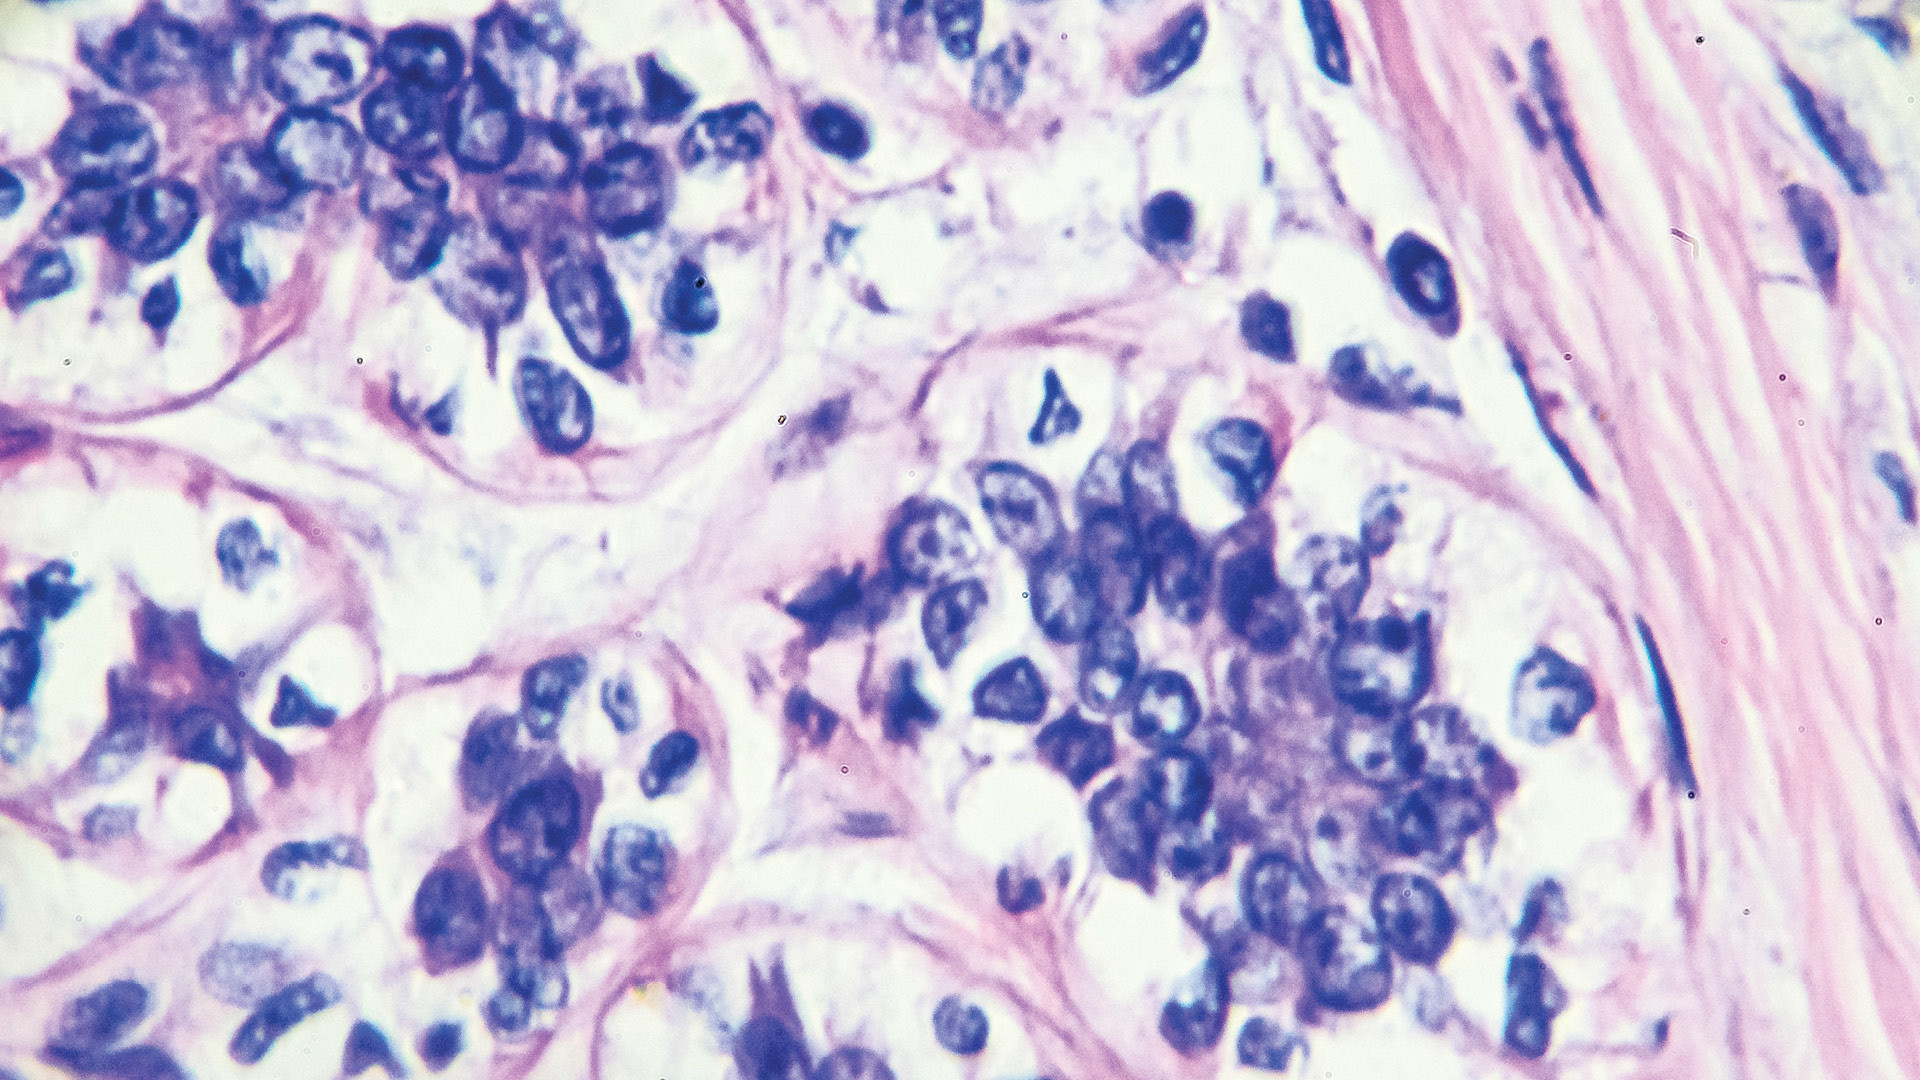

Additionally, we continue to learn more about the heterogeneity of breast cancer tumor biology and further understand that different cancer subtypes require dramatically different treatments. Therefore, a multidisciplinary approach to management in the preoperative setting is important to ensure optimal treatments and outcomes. New technologies also are providing exciting potential to further minimize surgical morbidity.

This article examines the importance of a multidisciplinary approach to breast cancer treatment, developments in axillary management, oncoplastic techniques, and emerging technologies such as robotic nipple-sparing mastectomy and tumor ablation.